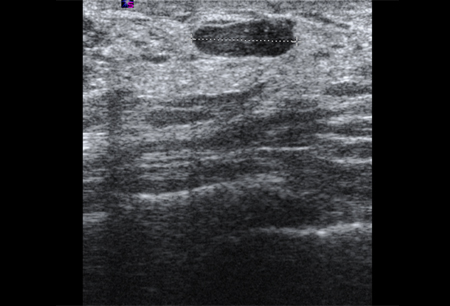

Imagen en ultrasonografía de un quiste simple

Cortesía del Dr. Lane Roland, University of Louisville; utilizada con autorización